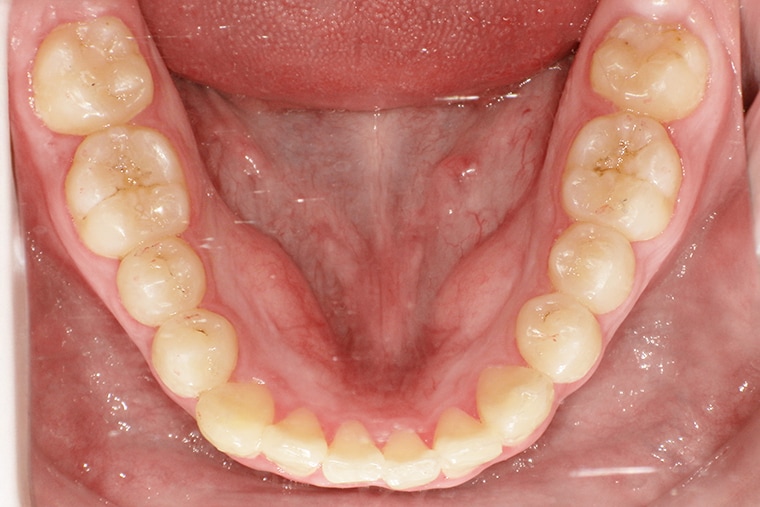

AFTER